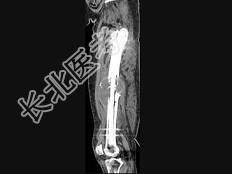

- 单项选择题男,18岁, 右股骨肿瘤术后,出现大腿中段疼痛, 夜间尤甚,结合CT图像, 最可能的诊断是 ( )